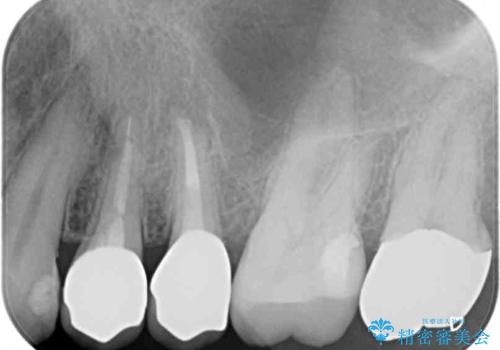

- 歯肉が退縮したためにクラウンの縁や歯根が見えてしまっていることを気にして来院された患者様です。

また、歯肉が黒く変色していることも気になるとのことでした。

仮歯に変える際に歯肉の一部を切除し、金属片による変色を除去した後、オールセラミッククラウンにて補綴することとしました。